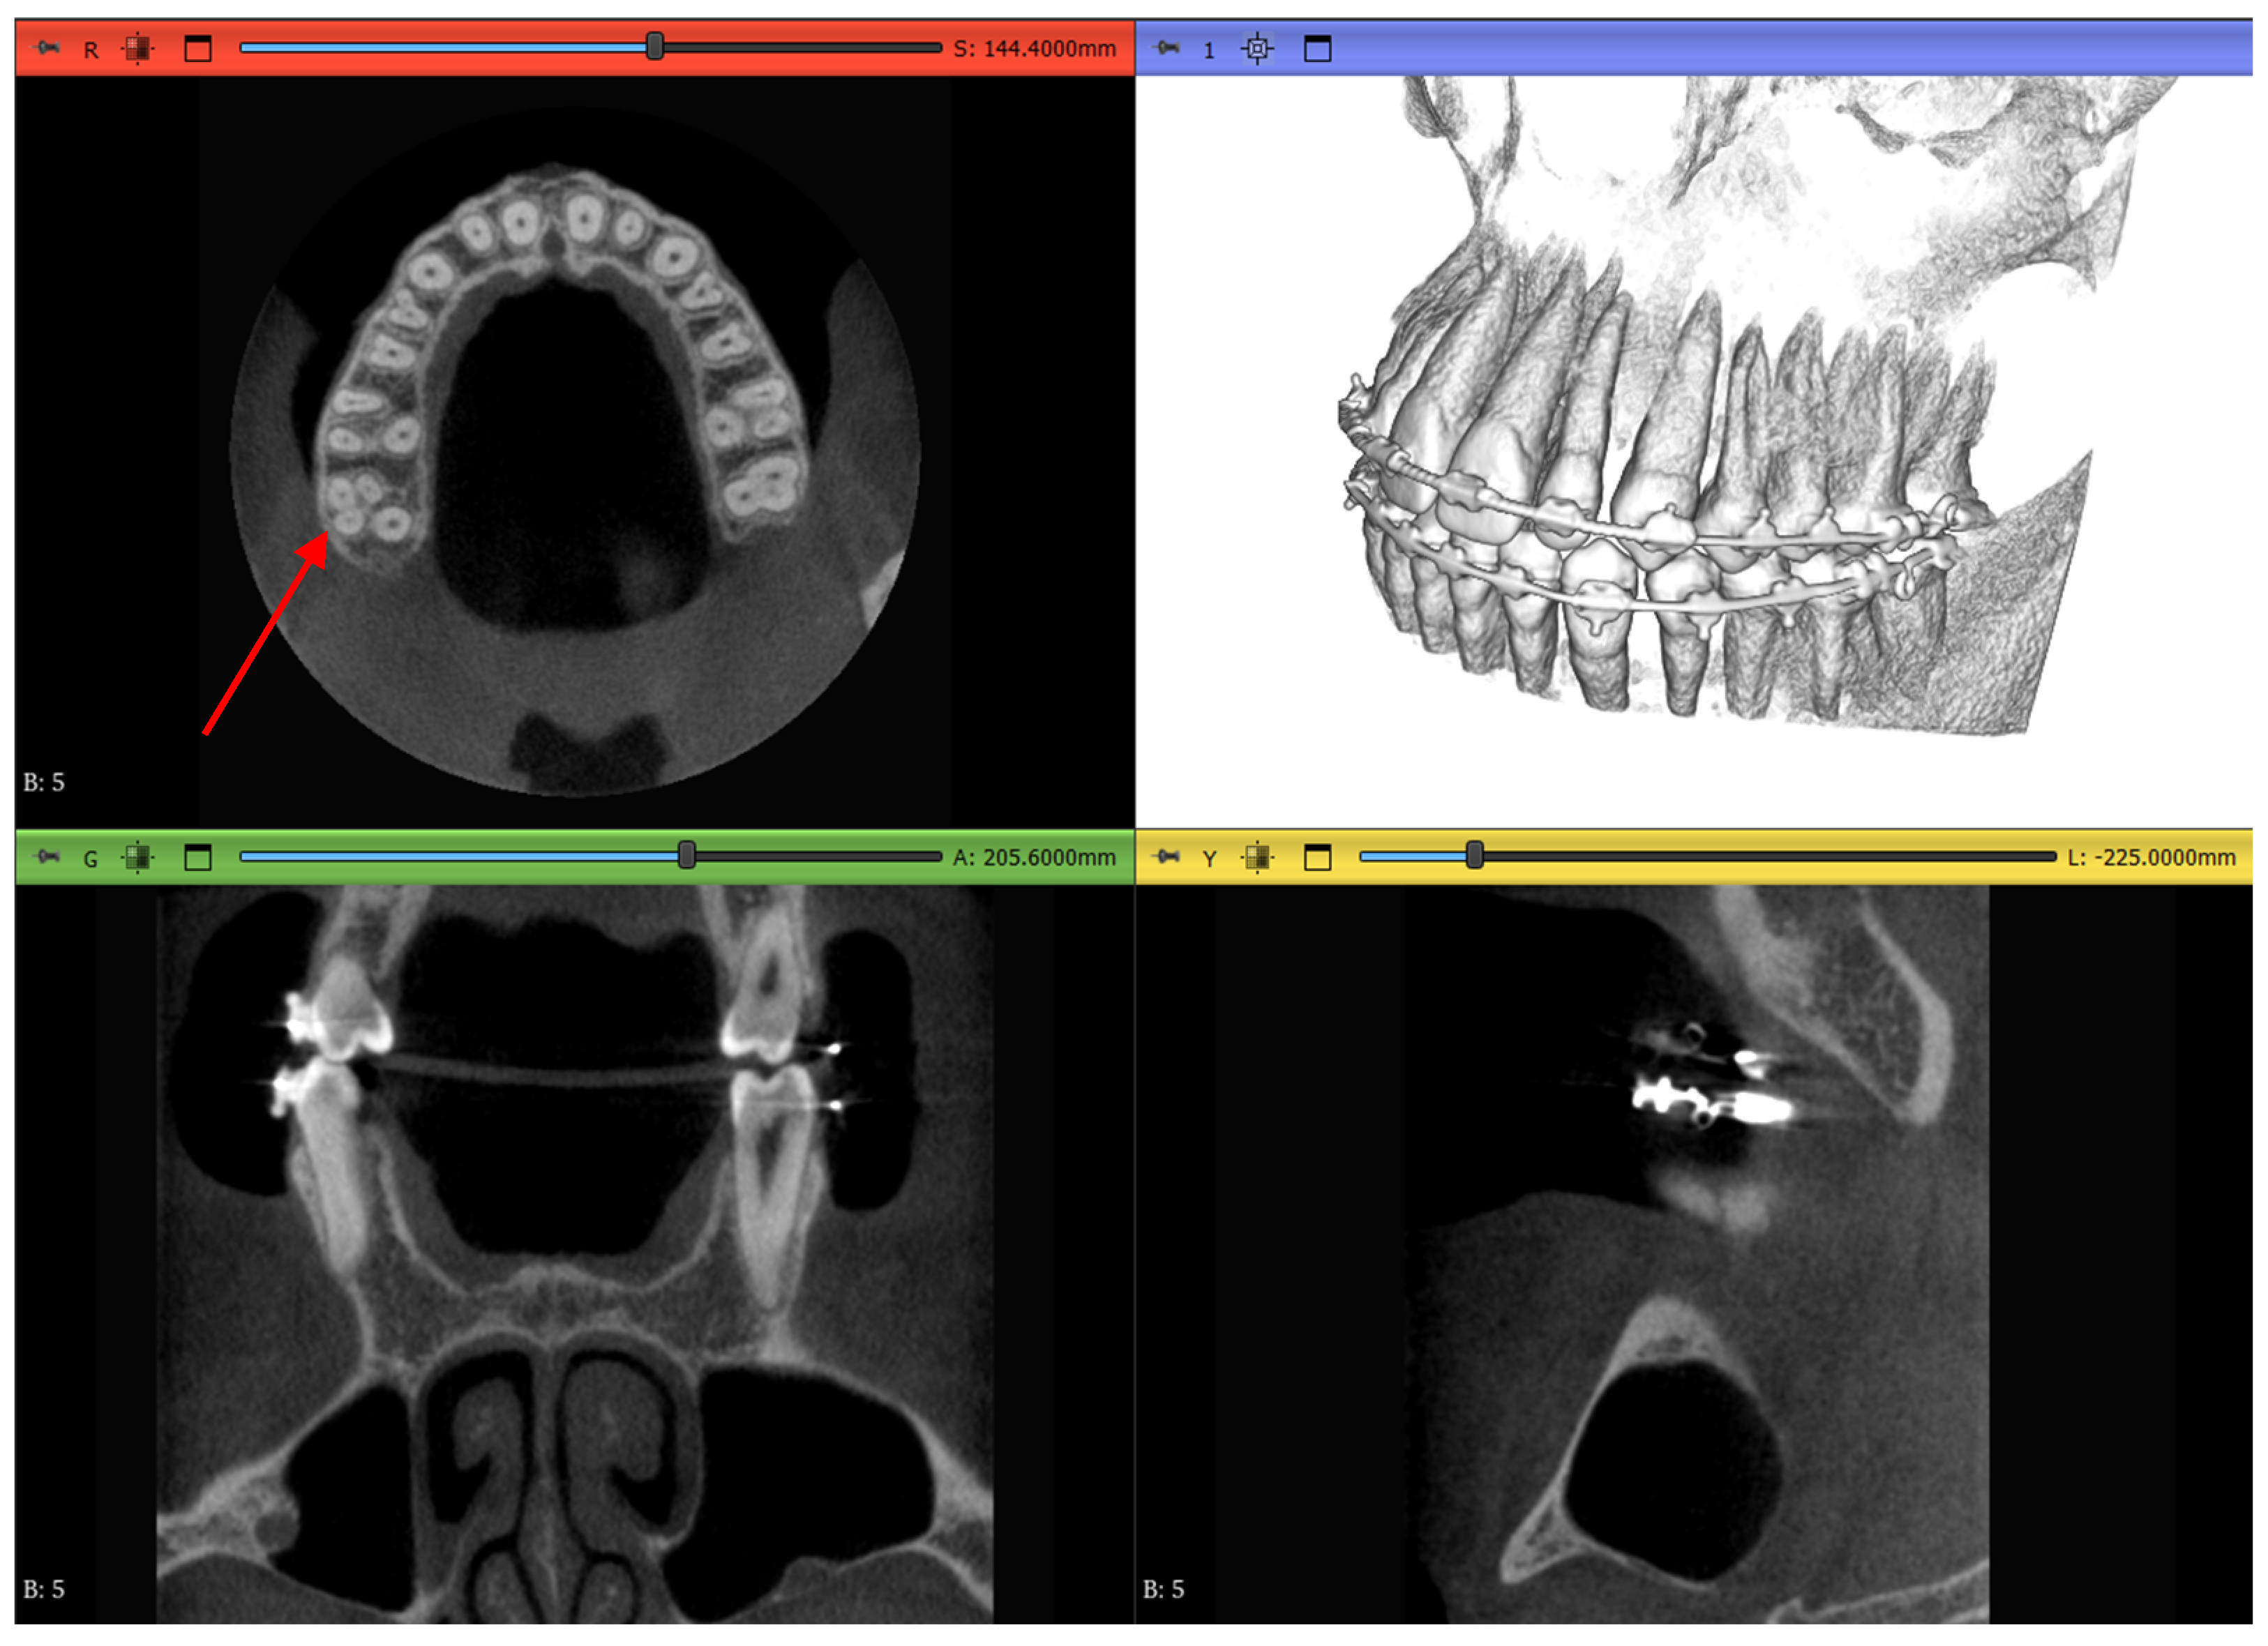

2.1. Datasets

2.3.1. Volume Cropping

2.3.2. Histogram Adjustment

2.3.3. Thresholding Masking